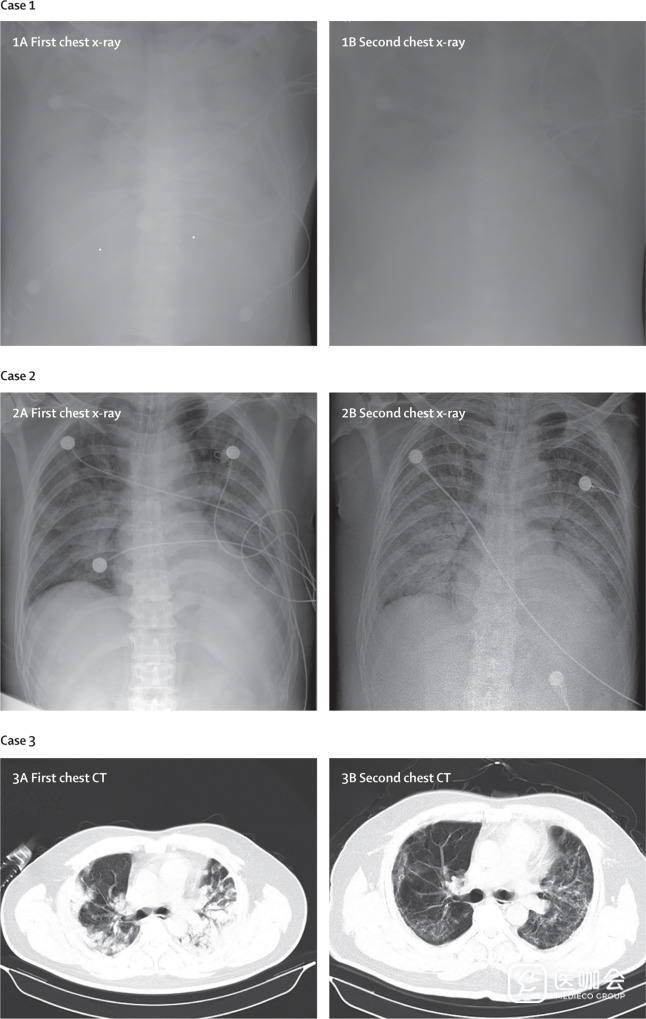

8、影像学检查:根据胸部X线和CT检查结果,74例(75%)患者出现双侧肺炎,14例(14%)患者表现为多发性斑点和磨玻璃样特征。